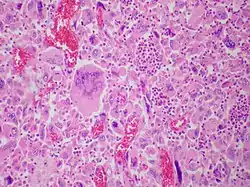

Pulmonary giant cell carcinoma represents a rare variety of non-small cell lung carcinoma that is characterized by the presence of numerous tumor giant cells and an influx of inflammatory cells that are mostly polymorphonuclear leukocytes admixed with macrophages. The dense oval aggregates of polymorphonuclear leukocytes seen in this image are probably located in the cytoplasm of tumor giant cells (emperiopolesis) that have been sectioned in a plane that does not include their nuclei.

The characteristic feature of this highly lethal malignancy is the distinctive light microscopic appearance of its extremely large cells, which are bizarre and highly pleomorphic, and which often contain more than one huge, misshapen, pleomorphic nucleus ("syncytia"), which result from cell fusion.

Compared to most other lung cancer variants, cells comprising GCCL tend to be much larger (up to 150 micrometers diameter, or even larger),[9] Both cells and nuclei show extreme variation in size distribution and shape. Carcinomatous giant cells carcinoma nuclei have been reported to average 5 times the size of lymphocyte nuclei.[8]

The cells from giant-cell carcinomas are anaplastic, and show no evidence of cell maturation or differentiation, lacking the cytological and tissue architectural characteristics of squamous cell carcinoma, adenocarcinoma, neuroendocrine carcinomas, or other more differentiated lung cancer cell types. They tend to be highly pleomorphic (i.e. variable in characteristics), but are most often round and/or polygonal in shape, with a relatively low nuclear-to-cytoplasmic ratio. When associated with spindle cells, as they very frequently are in tumors with mixed histology, malignant giant cells tend to form loosely cohesive aggregate structures on cytological examination. However, when a biopsy sample consists purely of malignant giant cells, the cells tend to be single and disaggregated.[1]

The chromatin of malignant giant cells tends to be hyperchromatic and coarsely clumped. Nucleoli are usually multiple and prominent.[9]

Both "tumor cell-tumor cell" and "leukocyte-tumor cell" emperipolesis (i.e. active penetration of the latter by the former) is very commonly seen in cases of GCCL.[12]